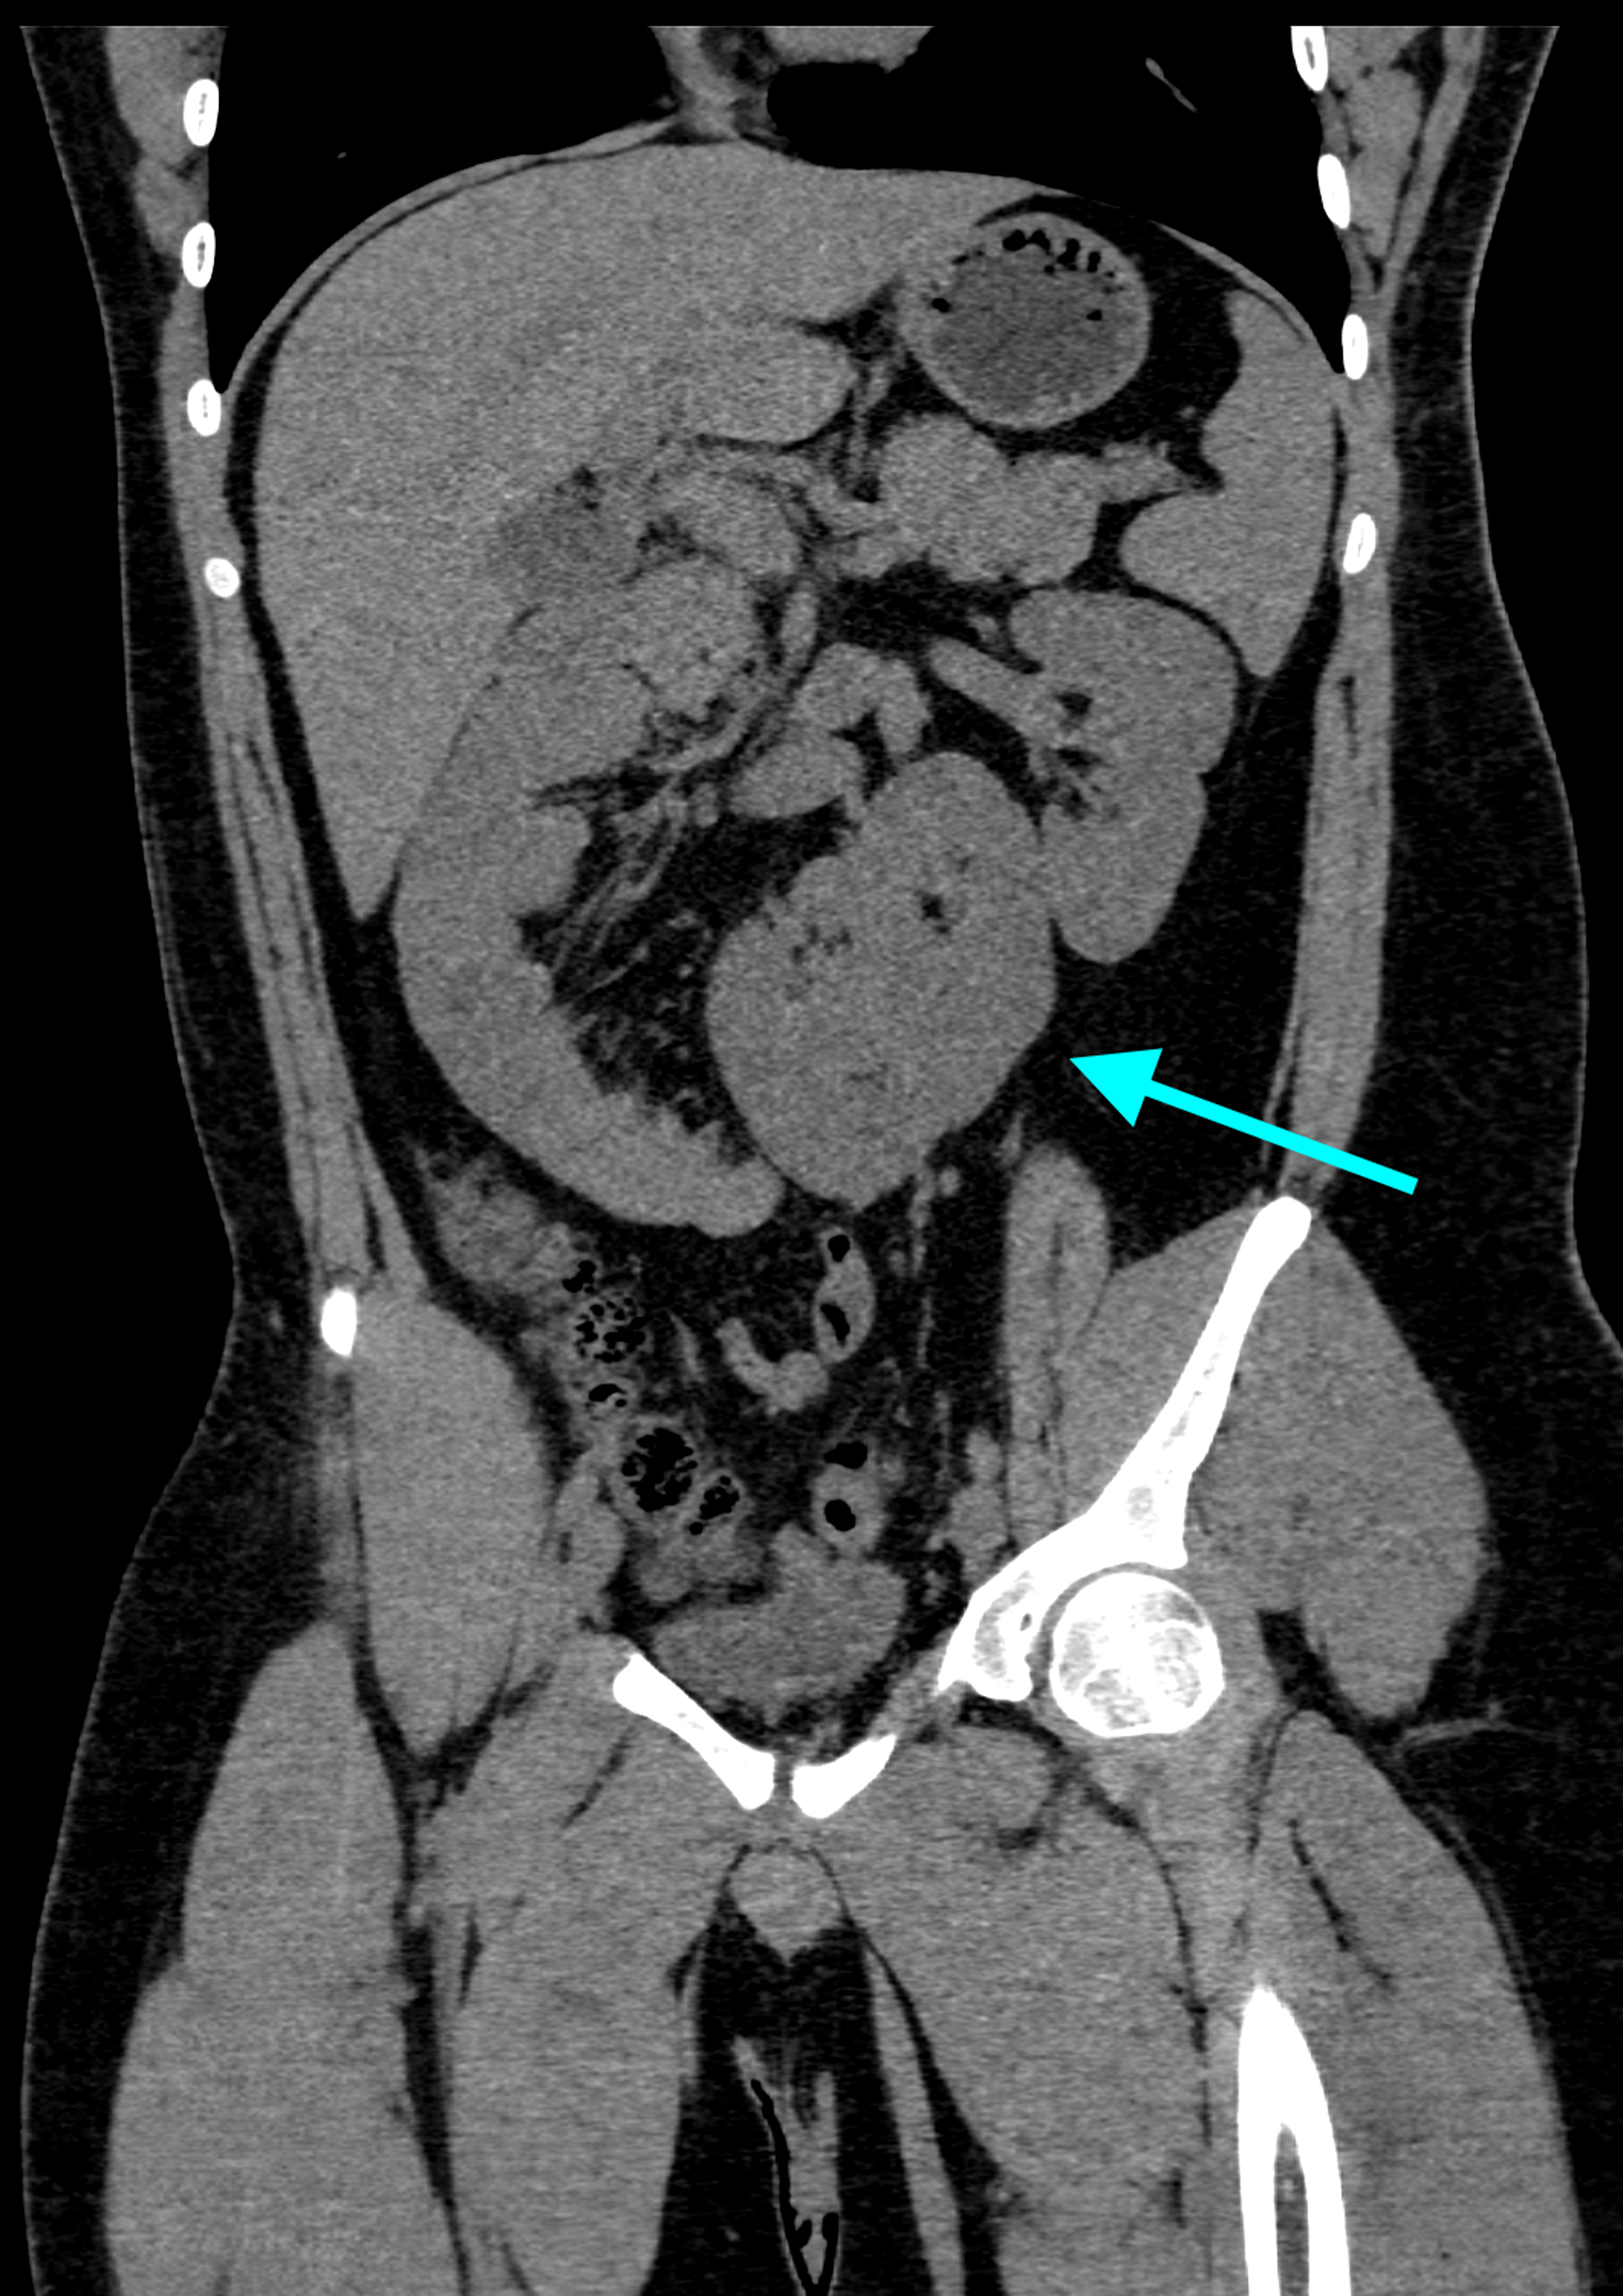

Supernumerary crossed fused renal ectopia Image Fused Supernumerary Kidney We present imaging findings in two cases of supernumerary kidneys—the first case is. a supernumerary kidney has a completely separate or partially fused renal parenchyma, a separate renal capsule. supernumerary kidney fused to the isthmus of a horseshoe kidney, with subsequent nephroblastoma, identified with dynamic renal scintigraphy a fused supernumerary kidney is a still rarer entity. . Fused Supernumerary Kidney.

Coronal reformatted CT of supernumerary kidney showing rotation anomaly Fused Supernumerary Kidney a supernumerary kidney has a completely separate or partially fused renal parenchyma, a separate renal capsule. supernumerary kidney is a rare anomaly of number where commonly a third extra kidney exists with its own. We present imaging findings in two cases of supernumerary kidneys—the first case is. a supernumerary kidney (sk) is an additional kidney with its. Fused Supernumerary Kidney.